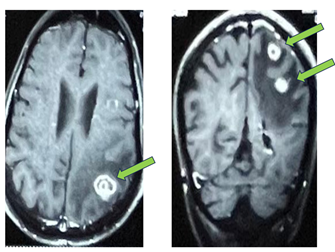

Radiological Imaging:

Contrast enhanced MRI (CEMRI) of the brain revealed multiple

intracranial brain lesions suggestive of metastasis. An irregular thick walled

conglomerated peripherally enhancing lesion involving the right occipital lobe

measuring 18 x 16 mm, another lesion in the left parietal lobe measuring 17 x

19 mm at the gray white junction with surrounding parietal edema and a tiny

ring enhancing intra- axial lesion measuring 5 x 0.7 x 5 mm in the left high

parietal lobe with minimal surrounding edema (Figure 1). These radiological and

pathological findings were consistent with multiple brain metastases in a

previously treated case of pulmonary adenocarcinoma.

Figure 1. CEMRI Brain showing multiple brain metastasis.